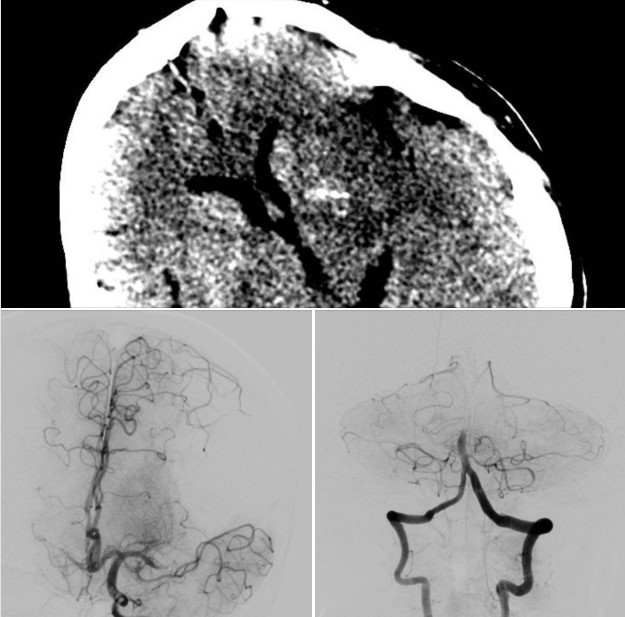

Đột quỵ cấp do tắc nhiều mạch máu, vấn đề nan giải với các bác sĩ

Đột quỵ cấp do tắc nhiều mạch máu là một trường hợp bệnh đột quỵ gây khó khăn cho các bác sĩ trong việc quyết định nên tái thông mạch máu nào trước là tốt nhất để cứu bệnh nhân.